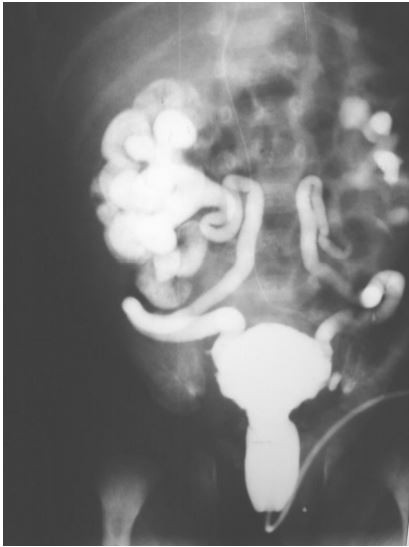

Lactente masculino apresenta infecção urinária de repetição e sepse. Tem diagnóstico pré-natal de hidronefrose bilateral. Realizou este exame radiológico contrastado.

Pode-se afirmar que:

Provas